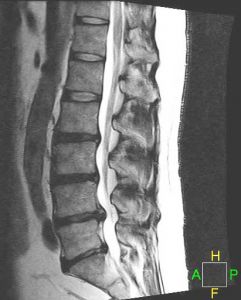

LUMBAR DISC HERNIATIONS ON MRI